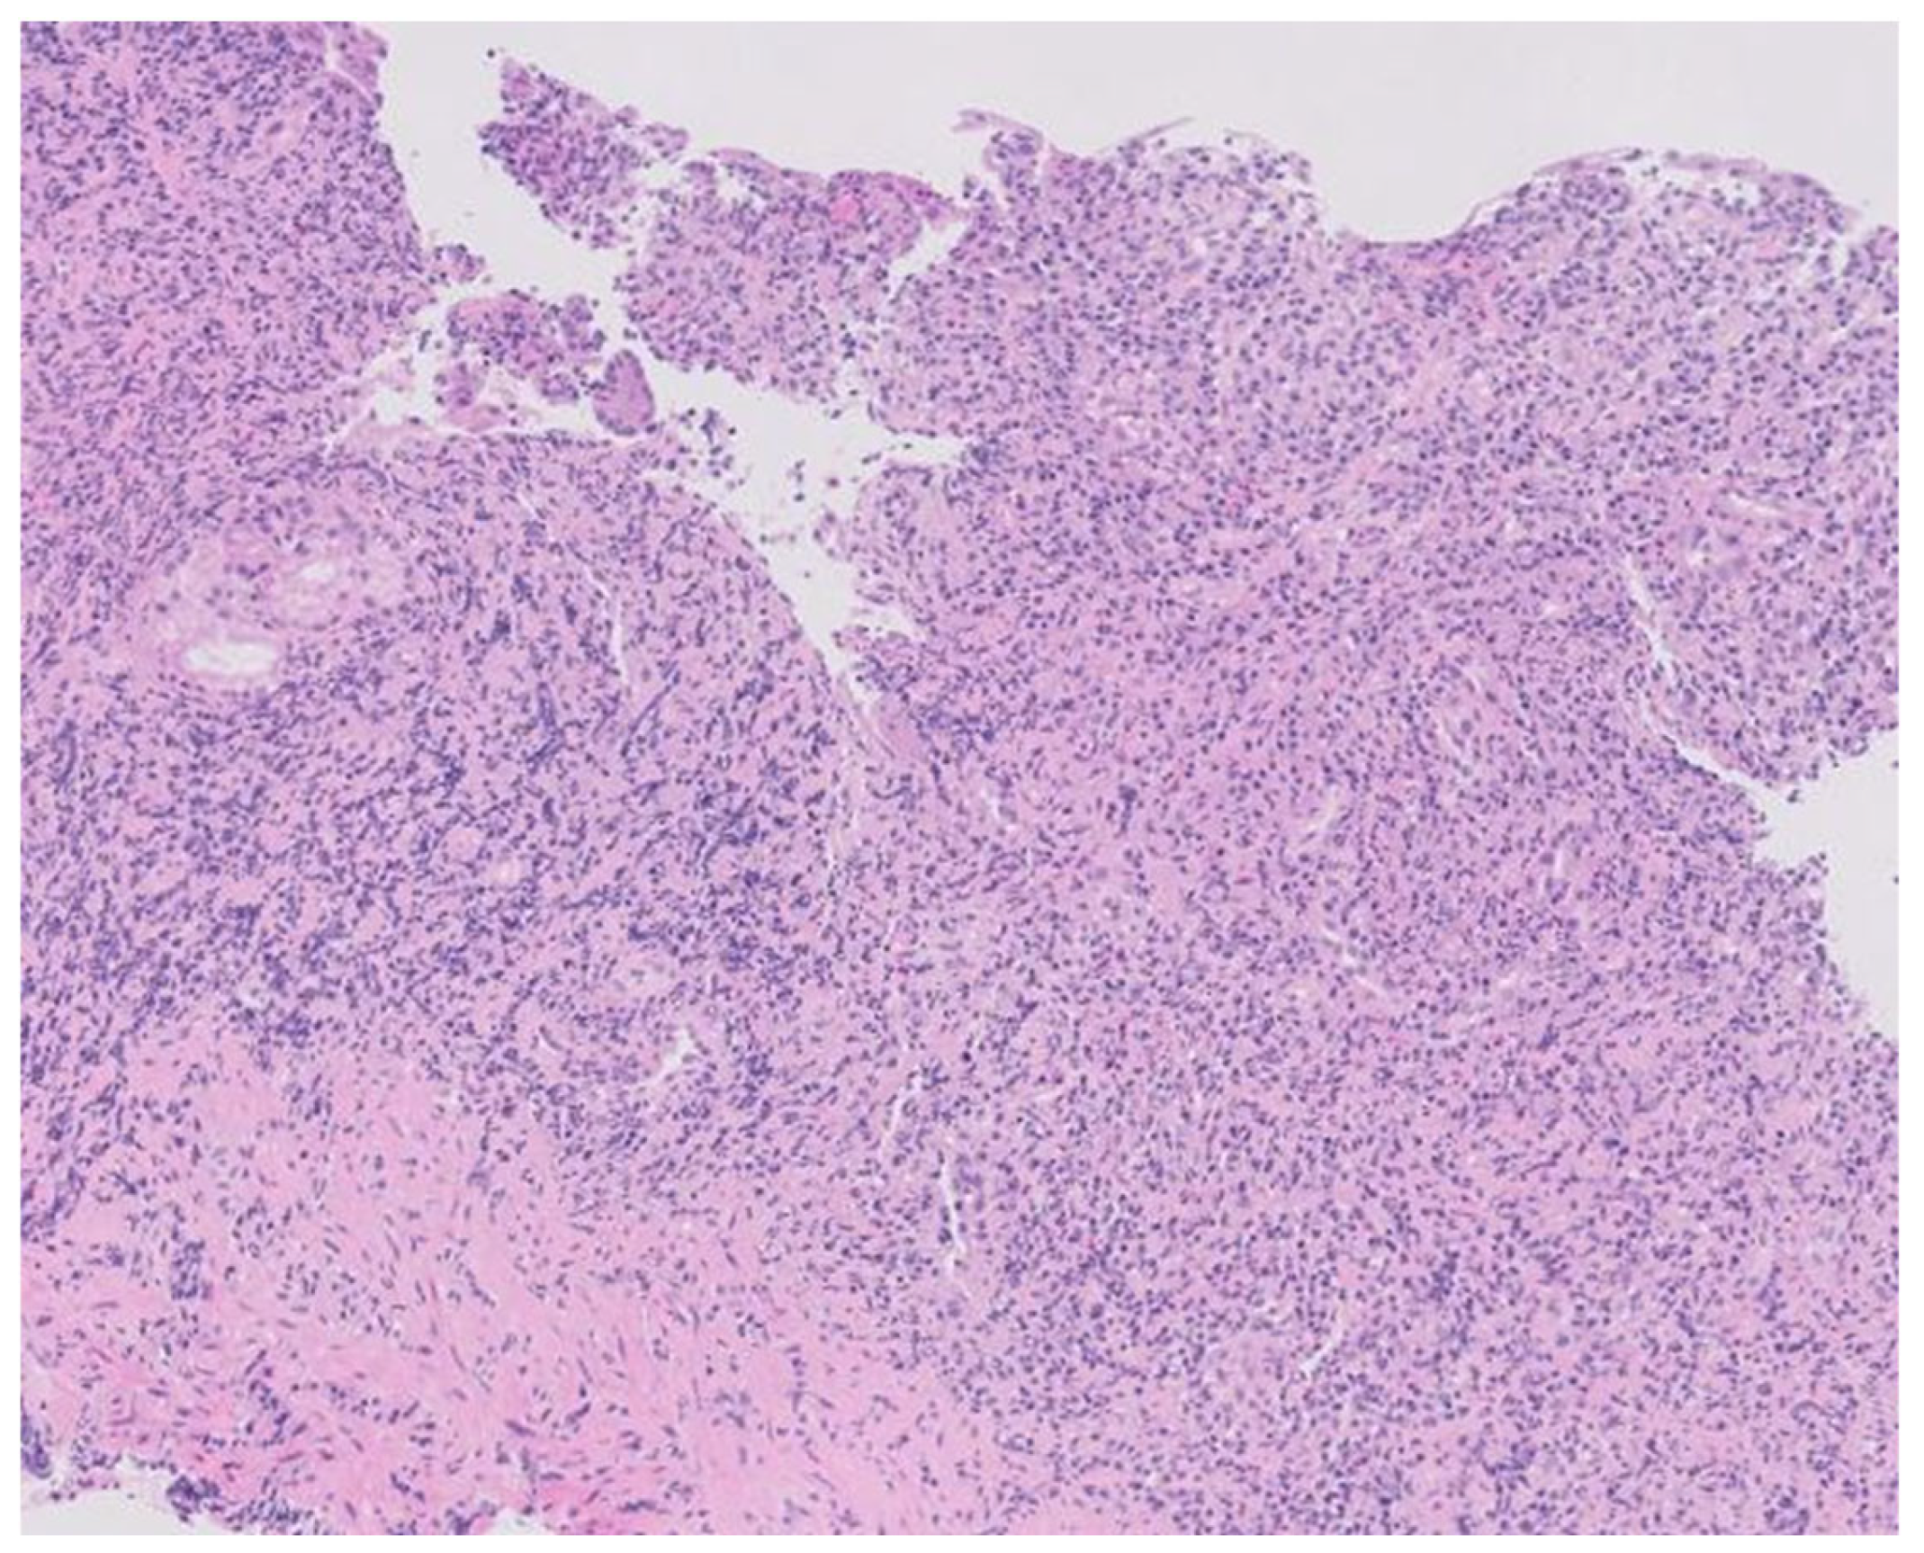

Confirmed syphilis infection prompted treatment with a single dose of 2.4 million units of intramuscular penicillin. Serologies for HIV and hepatitis C were negative, with confirmed protection against HAV and HBV. Gastric tissue biopsy results revealed ulcerated mucosa with a dense inflammatory infiltrate, while immunohistochemistry detected numerous Treponema pallidum spirochetes. Helicobacter pylori bacilli were also identified. The final diagnosis was syphilitic gastritis.

Figure 3. Histopathology of the gastric lesions revealing dense and diffuse lymphoplasmacytic and histiocytic inflammation in the lamina propria with effacement of the normal architecture (hematoxylin-eosin staining, X100).